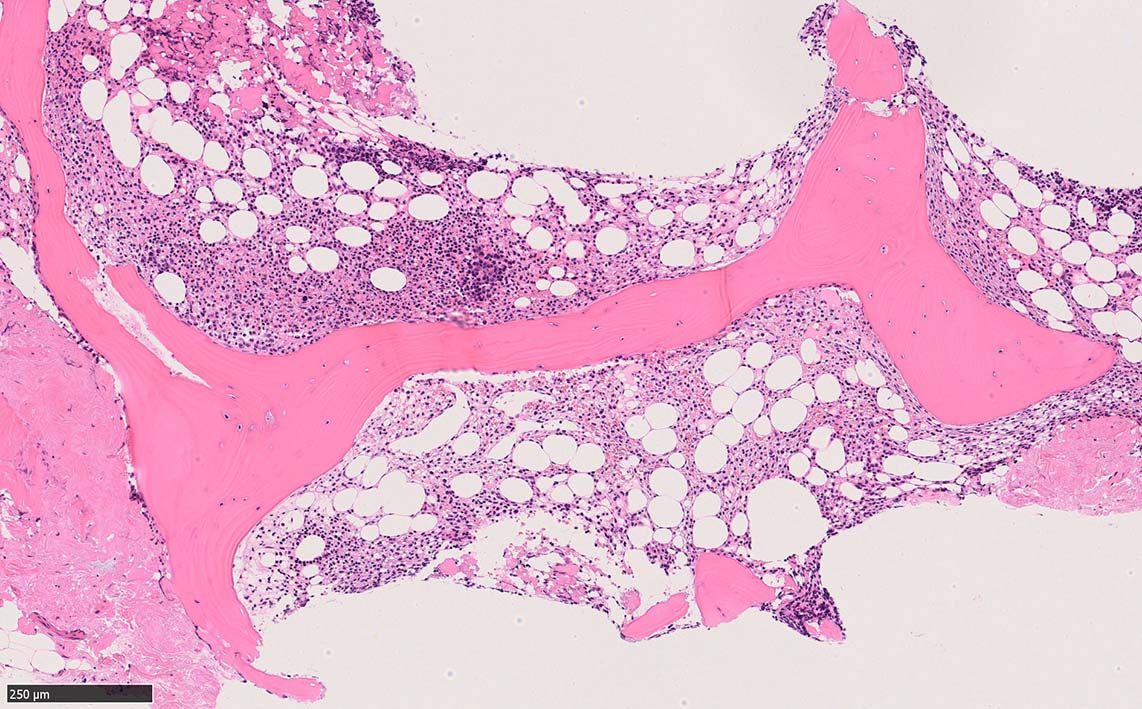

骨髄生検

bone marrow trephine biopsy: dry tapのため骨髄生検が行われる. cellularityは40-80%とhypercellular marrow. 流れのある細胞配列は線維化を疑わせる.

ASD-G 低倍率所見では赤芽球血島は幼若赤芽球の集簇巣が散在する, 顆粒球系細胞(ASDに赤く染色される)は減少,granulopoietic hypoplasiaを呈する.疎な集簇を示すmast cellsの増加がある.

ASD-G陰性の細胞がびまん性に増加しているように見える.

ASD-Giemsa陰性の細胞がシート状に増殖する. 核はクロマチン濃染, 核小体は不明瞭.類円形, 卵円形, くびれを持つ多稜形核, 長円形いびつで屈曲した核, など多彩. 細胞質は淡清色調, 広く淡明. 赤芽球血島は幼若赤芽球のみで形成される異形成像を示す. やや離れて成熟赤芽球が疎な集簇を示す.

Ag染色では, 疎な弾性線維が増生し,増殖細胞を小胞巣状に分画するいわゆる「lymphomatoid pattern」を呈する. 本例では, Mgkに異形成所見がある.